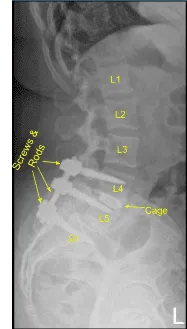

Transferred the data to the neuronavigation computer and image guided neuronavigation techniques were utilized for placement of the bilateral L4 pedicle screws which was accomplished by decorticating electric high-speed drill, cannulating the pedicles with the navigated pedicle finder, sounding for breaches, and measuring the depth using 5.5-mm tap and placing 6.5×45 mm titanium pedicle screws under neuronavigation guidance without difficulty. Neuromonitoring signals were table throughout.

Next, a new CT scan was obtained, which showed correct positioning of the new pedicle screws and interbody spacer. Bilateral transverse processes of L4, L5, and lateral ala were decorticated for arthrodesis. Pre-cut, pre-contoured rods reflected and placed across the tulips from L4 to S1 and secured with locking caps and finally tightened with the torque and anti-torque device.

Morselized autograft and allograft were placed into lateral gutters from L4 to S1 for the arthrodesis. Wound was irrigated copiously throughout the procedure. Vancomycin powder was applied. Closure was performed by a plastic surgeon.